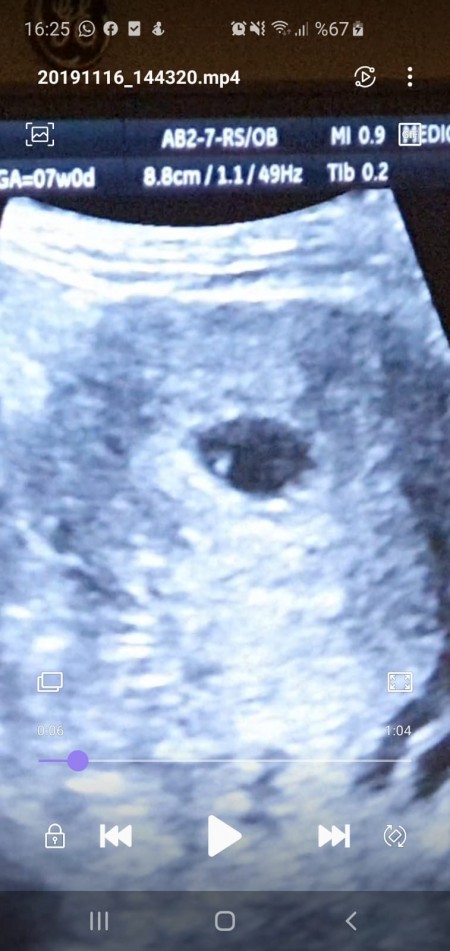

8 Haftalık Bebek Ultrasonda Görünmüyor

8 Haftalık Bebek Ultrasonda Görünmüyor.